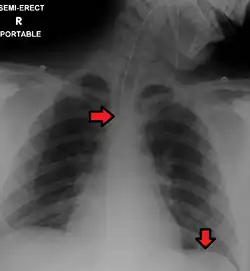

A chest radiograph, chest X-ray (CXR), or chest film is a projection radiograph of the chest used to diagnose conditions affecting the chest, its contents, and nearby structures. Chest radiographs are the most common film taken in medicine.

Chest radiographs are used to diagnose many conditions involving the chest wall, including its bones, and also structures contained within the thoracic cavity including the lungs, heart, and great vessels. Pneumonia and congestive heart failure are very commonly diagnosed by chest radiograph. Chest radiographs are also used to screen for job-related lung disease in industries such as mining where workers are exposed to dust.[3]